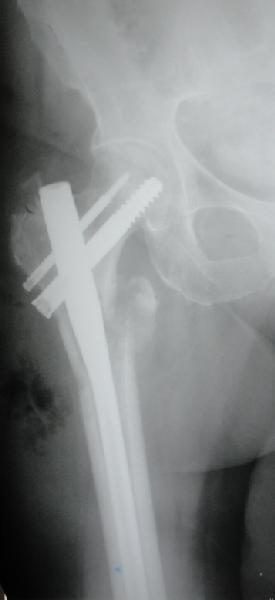

Перелом тут больше подвертельный. Нагрузка без торцевого упора на уровне перелома привела к телескопированию отломков на стержне. Ну и варус небольшой тоже свою лепту внес - если бы его не было, контактирующие латеральные стенки обоих отломков предотвратили бы укорочение, да и срослось бы за пару месяцев. А раз не срослось, упора отломков нет, более слабым местом оказались не нижние винты, а кость в головке и шейке. Так что надо было хотя бы удалить нижние винты до начала полной нагрузки.

На мой взгляд, причиной телескопирования явилось несоответствие диаметра гамма нэйл с диаметром канала подвертельного отдела бедра: обратите внимание на величину протрузии шеечного винта и величину медиализации дистального фрагмента - они одинаковы, смещение или телескопирование фрагментов происходило до того момента, пока гамма нэйл не упёрся в медиальный кортекс и образовалось пространство между латеральным

кортексом и латеральной поверхностью гвоздя.

В данном случае в головке бедра и в вертлужной впадине огромный дефект, навряд ли удалением импланта или заменой на другой можно сохранить сустав.

Вашему вниманию представляется похожий случай, пациентке 70, осложнился в течение одного месяца после операции. Ревизия с заменой сустава, кабельная фиксация на трохантер. При установке в дистальном диафизе обнаружен тонкий кортикальный слой и сделана профилактика от возможного перелома аллографтом.